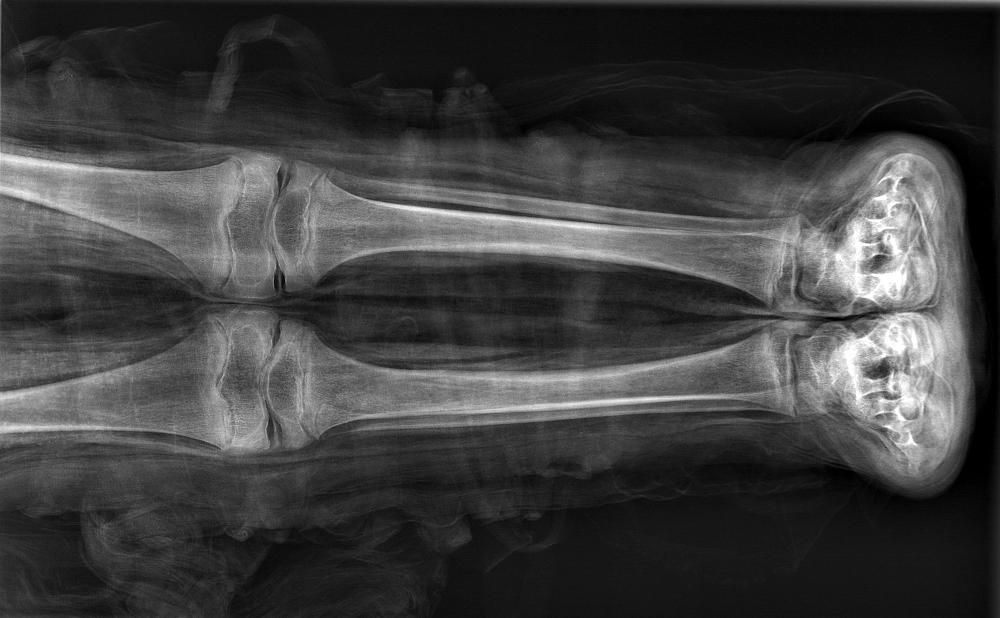

mummy, boy, human remains

- The mummy of a small boy.